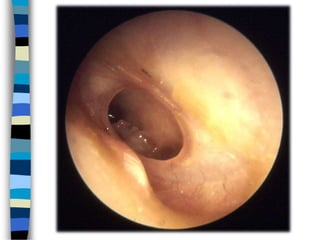

Хэнгэргэн хальсны цооролт

Хэнгэргэн хальсны татагдсан хэсгийн цооролт Хэнгэргэн хальсны суларсан хэсгийн цооролт

Эрүүл хэнгэрэг

Хэнгэргэн хальсны татагдсан хэсгийн

Хэнгэргэн хальсны суларсан хэсгийн

цооролт